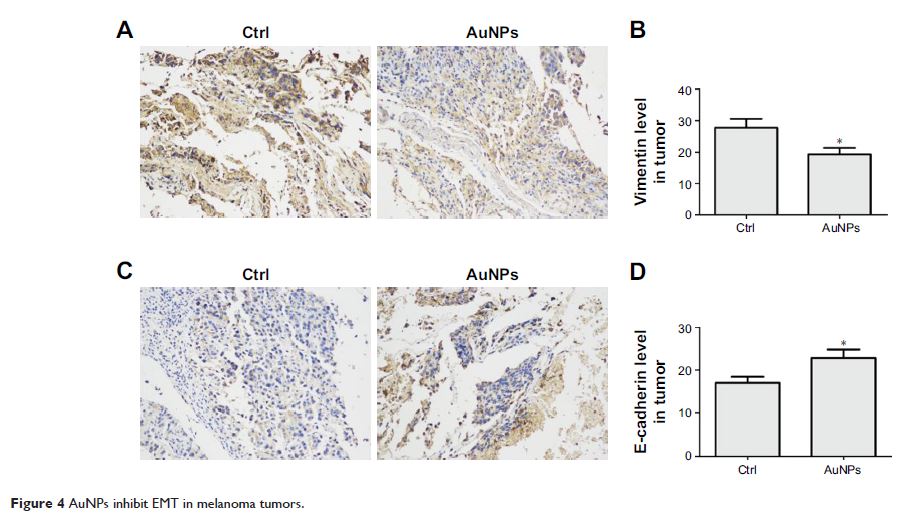

Original Research

通过肿瘤血管系统正常化和抑制上皮 — 间质转化,金纳米颗粒可削弱肿瘤的转移

- 作者:Wei Li, Xin Li, Shuhao Liu, Wende Yang, Fan Pan, Xiao-Yan Yang, Bin Du, Li Qin, Yunlong Pan

- 期刊:International Journal of Nanomedicine